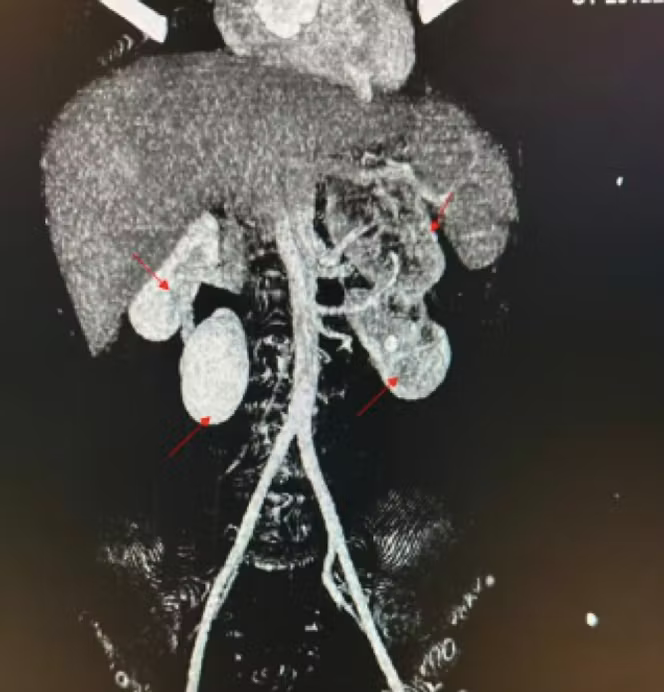

C’est l’histoire d’un homme de 63 ans qui consulte aux urgences pour une douleur lombaire gauche persistante. L’examen clinique et les analyses sanguines sont normaux. Rien, à première vue, ne laisse présager une anomalie anatomique. Et pourtant, l’échographie abdominale met en évidence une configuration inattendue : non pas deux reins, mais trois, dont deux sont fusionnés en une structure en fer à cheval.

Le scanner confirme la présence de trois reins distincts : deux reins fusionnés dans la fosse rénale gauche et un troisième rein en position médiane, chacun doté d’une vascularisation indépendante. La fonction rénale est globalement normale. Quelques petits calculs, non obstructifs, sont observés dans les reins gauches.

Ce cas, rapporté en mars 2026 dans la revue Radiology Case Reports par des radiologues marocains de l’hôpital Ibn Sina à Rabat, associe deux anomalies congénitales déjà rares en elles-mêmes (rein surnuméraire et rein en fer à cheval), aboutissant à une configuration d’une exceptionnelle rareté.